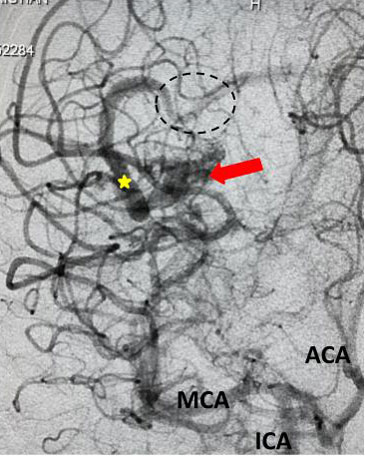

The patient was taken to the angio-suite where an angiogram confirmed a high flow, high pressure AVM fed primarily by the posterior cerebral artery with a small collateral from the middle cerebral artery (Fig 2 and 3). The AVM drained into a tortuous, partially occluded and stenotic single draining vein.

Fig 2. AP view, mid-arterial phase of a right internal carotid artery (ICA) injection. The large tortuous draining vein (yellow star) with the suggestion of clot (dotted circle) can be seen. AVM nidus (red arrow), MCA (middle cerebral artery, ACA (anterior cerebral artery).